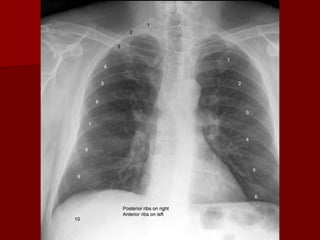

Inspiration:

The volume of air in the hemithorax will affect the

configuration of the heart in relation to cardiac size.

The vascular pattern in the lung fields will be

accentuated with a shallow inspiration.

The level of inspiration can be estimated by

counting ribs.

Visualization of nine posterior ribs, or seven

anterior ribs on an upright PA radiograph projecting

above the diaphragm would indicate a satisfactory

inspiration